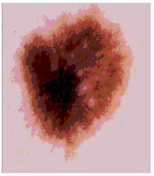

![]() | ![]() | ![]() | ![]() |

| Img1 | --- Pixel Intensity (0–255) ---> | ||

| Img2 | --- Pixel Intensity (0–255) ---> | ||

| Img3 | --- Pixel Intensity (0–255) ---> | ||

| Img4 | --- Pixel Intensity (0–255) ---> | ||

| Img5 | --- Pixel Intensity (0–255) ---> | ||

| Img6 | --- Pixel Intensity (0–255) ---> | ||

| Img7 | --- Pixel Intensity (0–255) ---> | ||

| Img8 | --- Pixel Intensity (0–255) ---> | ||

| Img9 | --- Pixel Intensity (0–255) ---> | ||

| Img10 | --- Pixel Intensity (0–255) ---> | ||